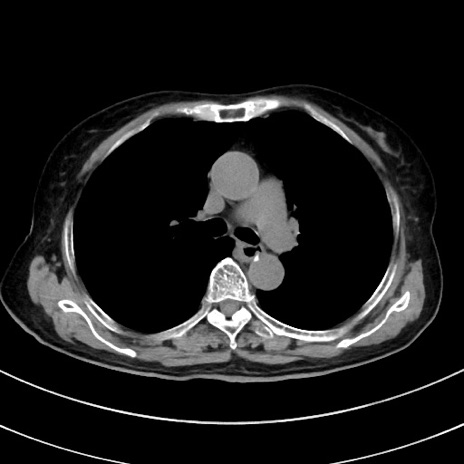

症例33(横断像)

【症例】70歳代 女性

【主訴】心窩部痛

【現病歴】延髄病変の精査・加療にて神経内科入院中。本日より心窩部痛あり。

【既往歴】虫垂炎

【身体所見】右下腹部を中心に圧痛と反跳痛あり。

【データ】WBC 10900、CRP 0.02